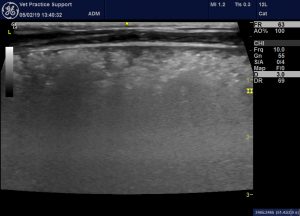

But on the right:

And a frozen image of another angle on the same area (labelled erroneously as left):

….there is a large consolidated area which appears to be delineated by the pleural margins of the middle lobe. Normally-arranged vessels and bronchi are present: which tends to suggest it’s not neoplastic. Neither is there the typical serrated margins to the consolidated area which we see with pneumonia. In particular, the frozen image looks very atypical for pneumonia: diffuse, indistinctly-marginated hypoechoic change. I have seen angiostrongylosis look similar to this. However, angiostrongylosis would be expected to affect both lungs if it were this severe.

There is a further clue to possible torsion in that video clip. In a longitudinal plane view like that the caudal edge of the lung should have an angular margin: rather than the rounded profile that we see in this case.